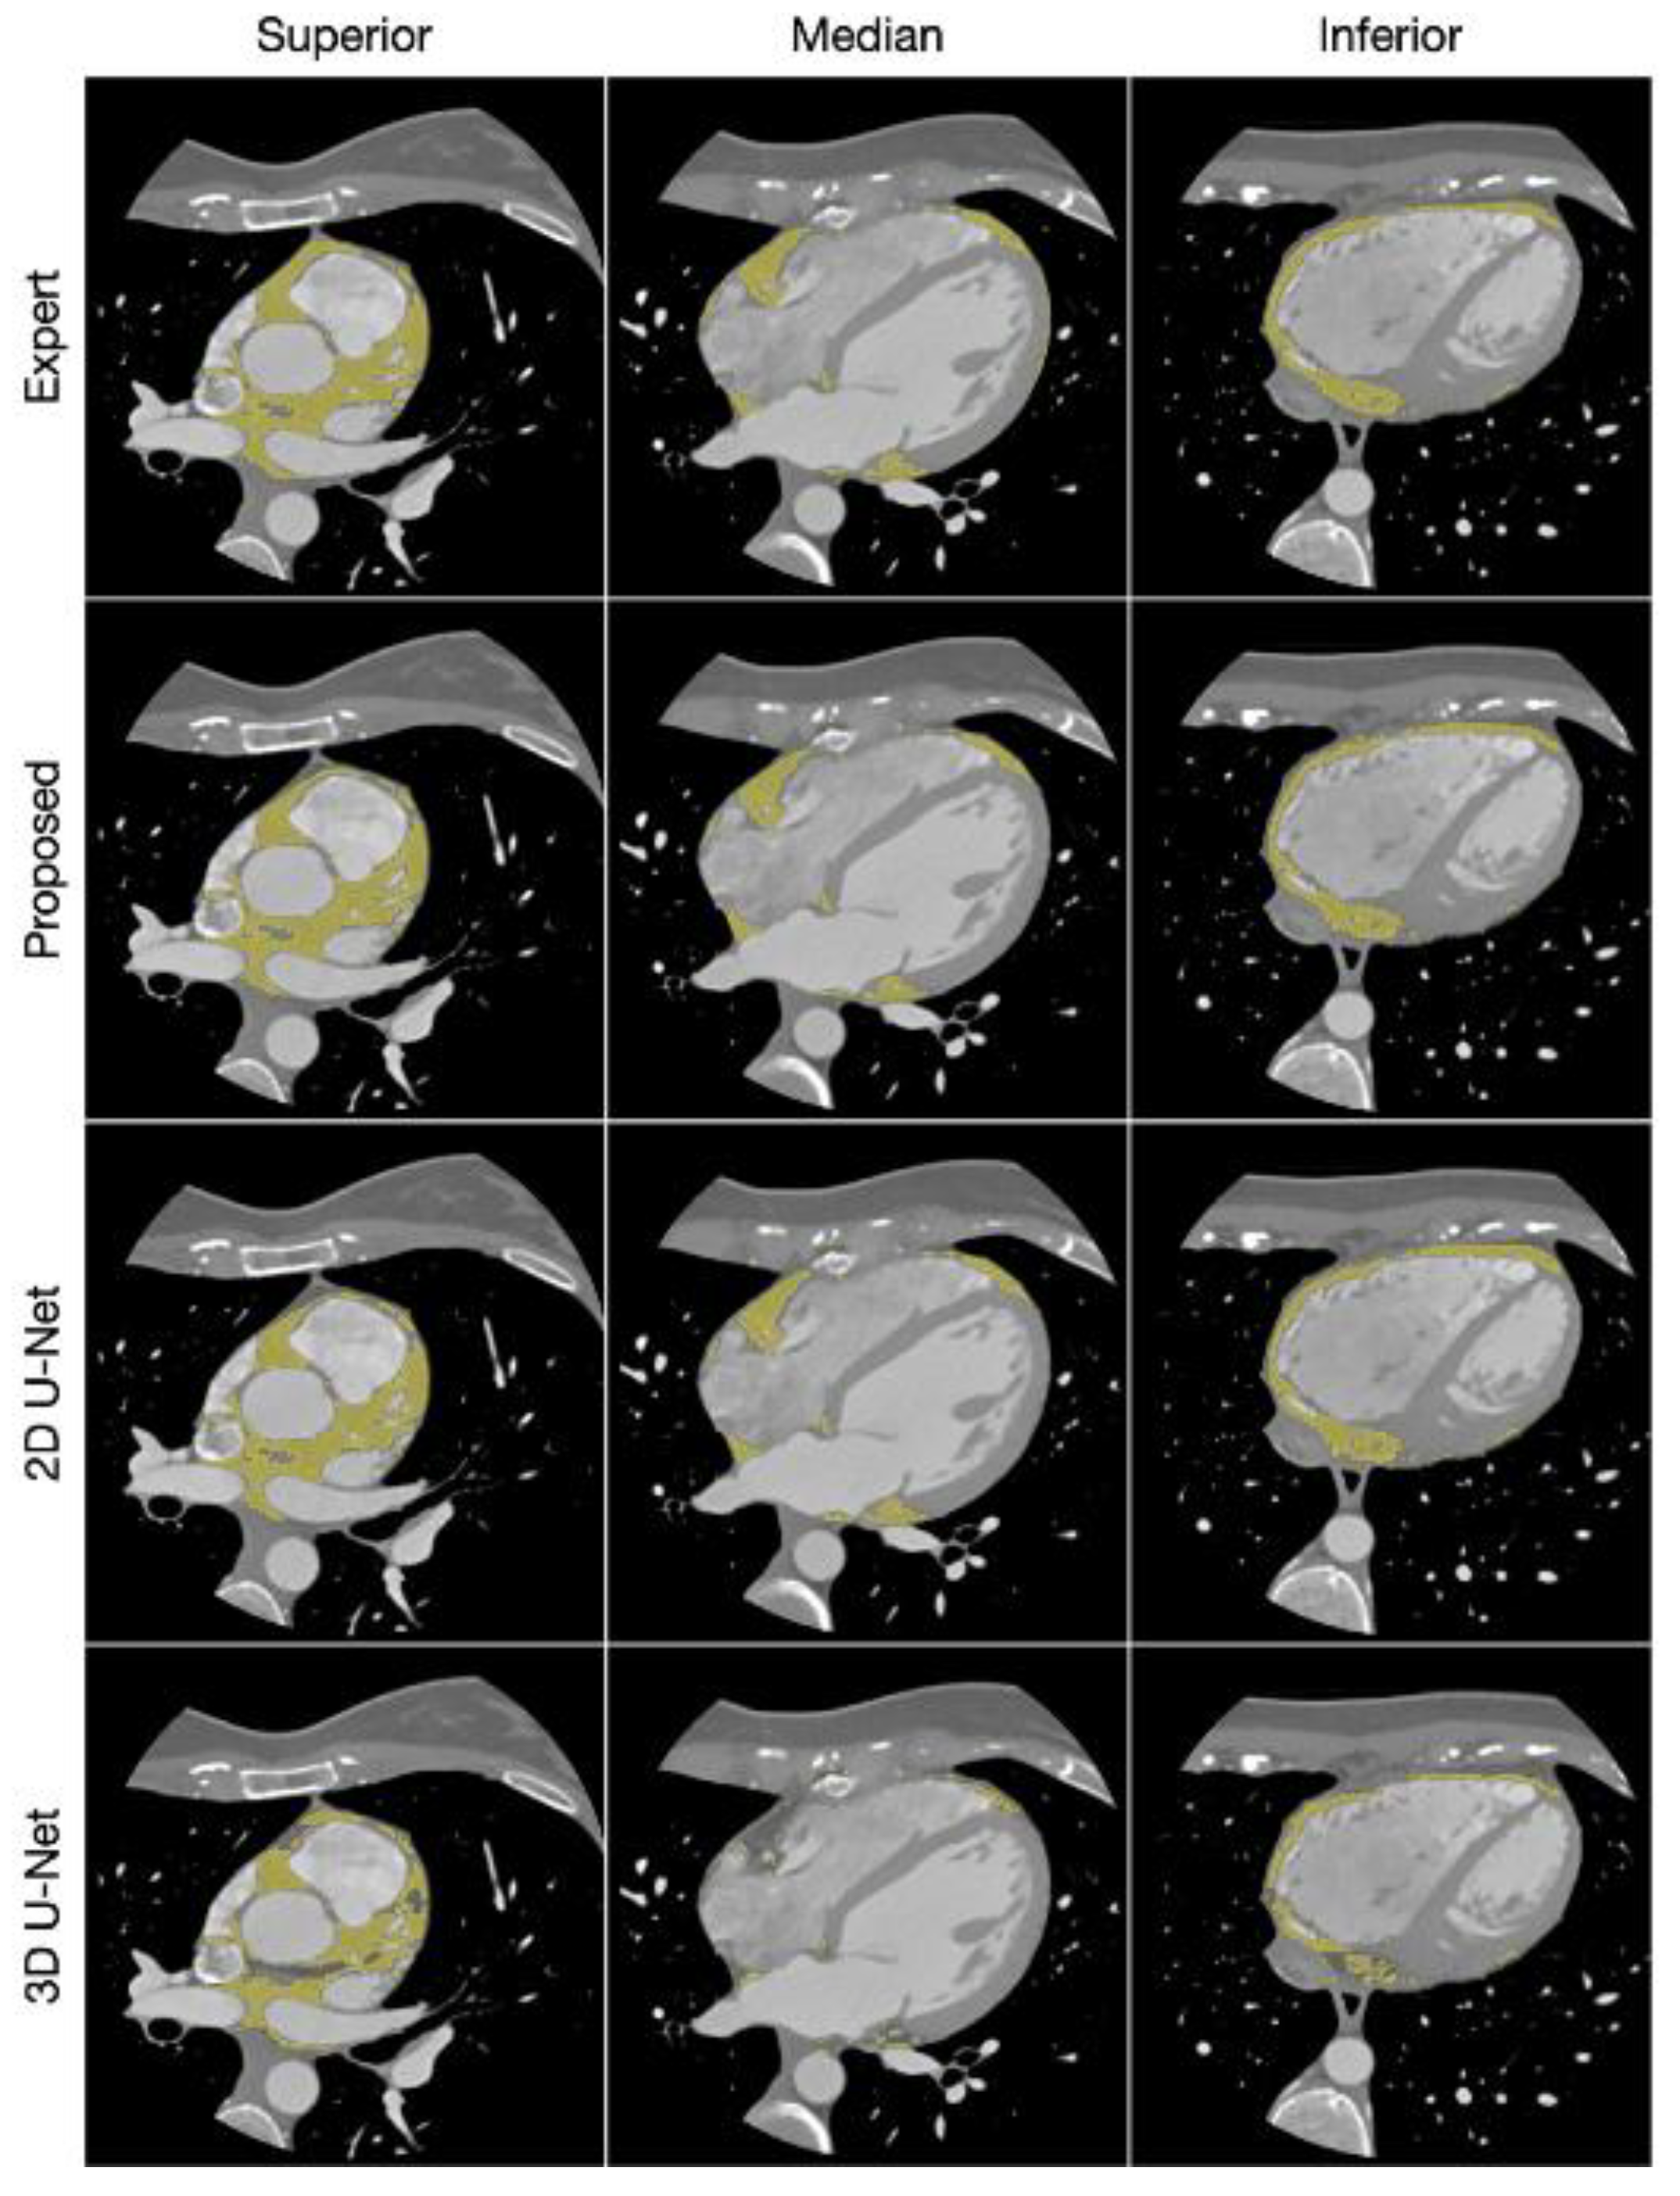

- Kulasekara, M.; Dinh, V.Q.; Fernandez-del-Valle, M.; Klingensmith, J.D. Comparison of two-dimensional and three-dimensional U-Net architectures for segmentation of adipose tissue in cardiac magnetic resonance images. Med Biol Eng Comput. 2022, 60, 2291–2306. [Google Scholar] [CrossRef]

- Benčević, M.; Galić, I.; Habijan, M.; Pižurica, A. Recent Progress in Epicardial and Pericardial Adipose Tissue Segmentation and Quantification Based on Deep Learning: A Systematic Review. Applied Sciences. 2022, 12, 5217. [Google Scholar] [CrossRef]

- Greco, F.; Salgado, R.; Van Hecke, W.; Del Buono, R.; Parizel, P.M.; Mallio, C.A. Epicardial and pericardial fat analysis on CT images and artificial intelligence: A literature review. Quant Imaging Med Surg. 2022, 12, 2075–2089. [Google Scholar] [CrossRef]

- He, X.; Guo, B.; Lei, Y.; et al. Automatic epicardial fat segmentation in cardiac CT imaging using 3D deep attention U-Net. In: Landman, B.A.; Išgum, I.; eds. Medical Imaging 2020: Image Processing. SPIE; 2020:84. [CrossRef]

- Bencevic, M.; Habijan, M.; Galic, I. Epicardial Adipose Tissue Segmentation from CT Images with A Semi-3D Neural Network. In: 2021 International Symposium ELMAR. IEEE; 2021:87-90. [CrossRef]

- Commandeur, F.; Goeller, M.; Razipour, A.; et al. Fully Automated CT Quantification of Epicardial Adipose Tissue by Deep Learning: A Multicenter Study. Radiology: Artificial Intelligence. 2019, 1, e190045. [Google Scholar] [CrossRef]